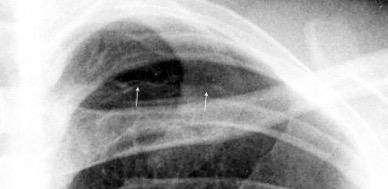

En el hemotórax, los elementos formes de la sangre tienden a depositarse en la parte más declive

Polireddy K et al. Blunt thoracic trauma: role of chest radiography and comparison with CT findings and literature review . Emerg Radiol 2022.

Neumo-Hemotórax

Sin fracturas: 6,7%

1-2 fracturas: 24,9% + de 3 fracturas:81,4%

Colección pleural

Hemorrágica.30-70 UH

Extravasación iv con sangrado activo.>90 UH “Simpático”..<15 UH